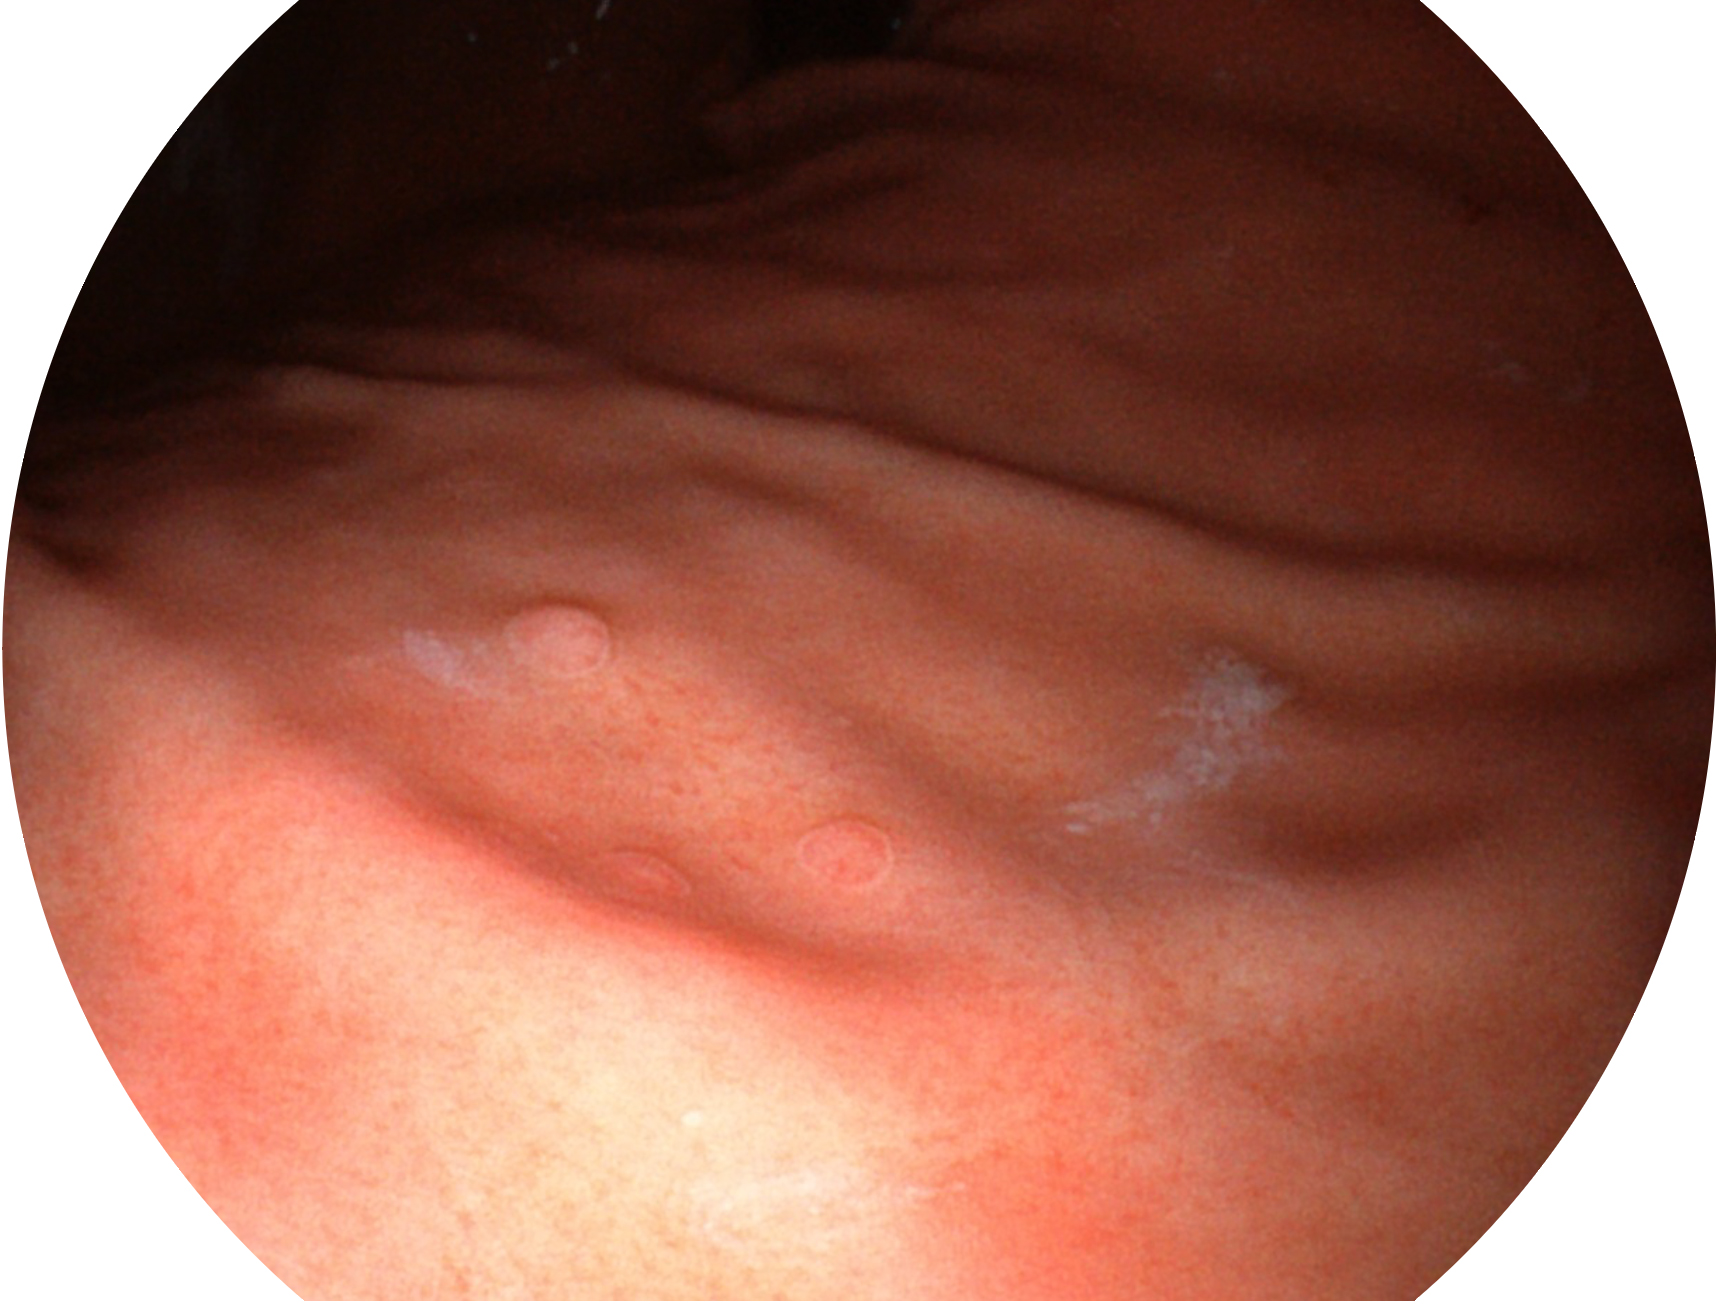

亚星官网新开发的内镜染色技术,主要是基于多波长LED 光源的开发,VLS-55Q 四波长LED 光源是由四个不同颜色的LED光按照相应照明模式所规定的特定发光比例进行合束后形成,合束后形成的照明光的光谱由红光、绿光、蓝光及蓝紫光这四个不同的波段范围构成。具有更高光谱自由度,通过光谱比例的控制,实现了聚谱成像技术,英文全称为“Spectral Focused Imaging, SFI”,缩写为“SFI”和光电复合染色成像技术,英文全称为“Versatile Intelligent Staining Technology, VIST”,缩写为“VIST”。